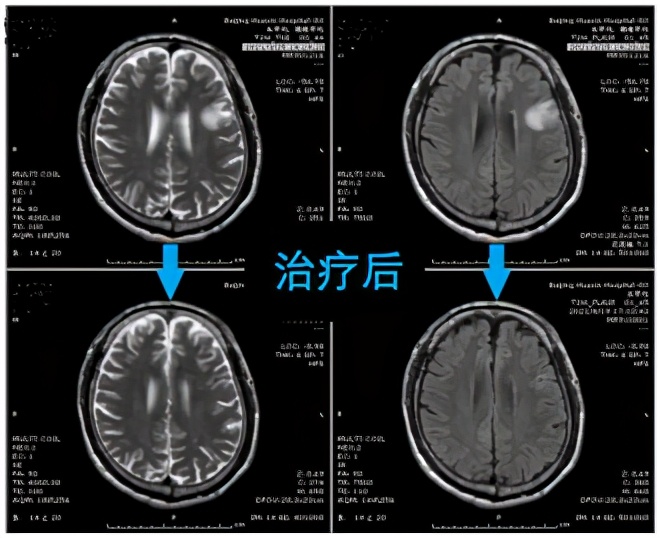

与患者及家属充分沟通后给予驱虫治疗,10天后患者头痛症状逐渐好转,未再发作癫痫。复查核磁检查,病灶较前明显缩小,更验证了神经内科医师此前做出的诊断。